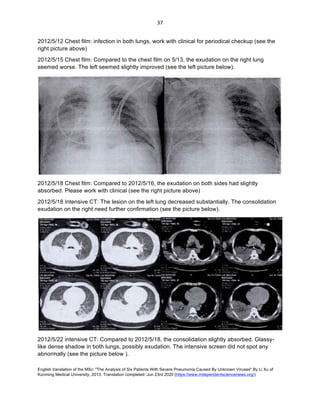

2012/5/12 Chest film: infection in both lungs, work with clinical for periodical checkup (see the

right picture above)

2012/5/15 Chest film: Compared to the chest film on 5/13, the exudation on the right lung

seemed worse. The left seemed slightly improved (see the left picture below).

2012/5/18 Chest film: Compared to 2012/5/16, the exudation on both sides had slightly

absorbed. Please work with clinical (see the right picture above)

2012/5/18 Intensive CT: The lesion on the left lung decreased substantially. The consolidation

exudation on the right need further confirmation (see the picture below).

2012/5/22 intensive CT: Compared to 2012/5/18, the consolidation slightly absorbed. Glassy-

like dense shadow in both lungs, possibly exudation. The intensive screen did not spot any

abnormally (see the picture below ).